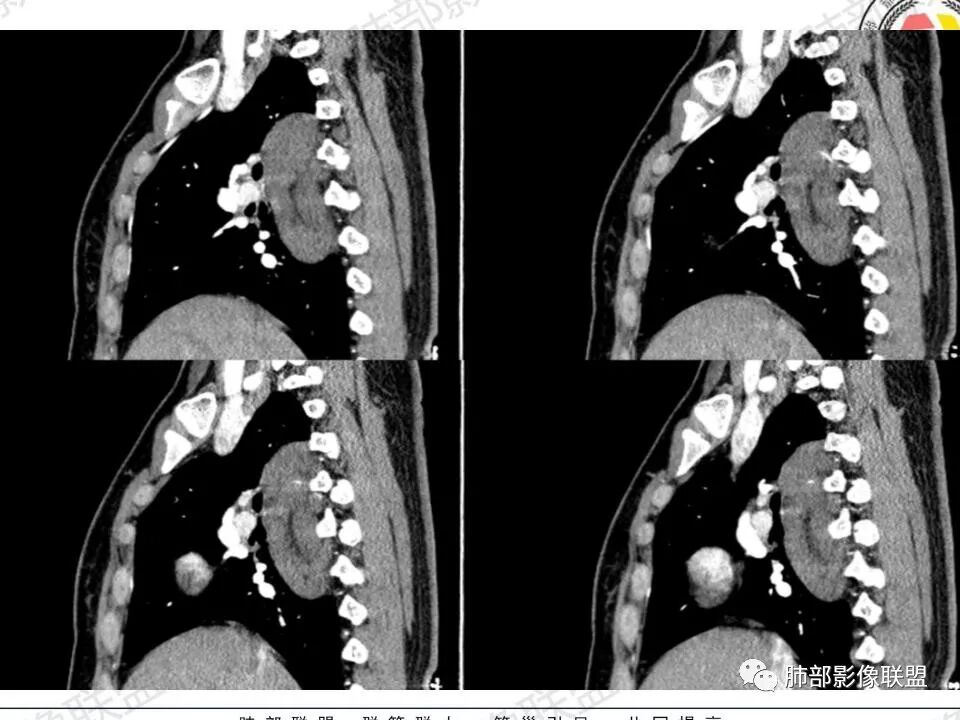

2.右后纵隔脊柱旁上下方向贴伏块影,“肾”形外观,边界清晰,密度不均,中央区域见脂肪密度影引向椎体前方,未见液性密度管腔影及钙化。

1.肿块未横向经椎间孔延入椎管,或形成所谓“哑铃状”外观等,没有显示出沿脊神经根生长特征。长轴顺脊柱贴行恰好与交感神经路径相一致。

瘤体体积常较大,大部分有完整包膜,边界清楚,可沿周围组织间隙嵌入性生长,由于肿瘤质地较软,使得肿瘤可呈多种形态,其易沿着周围组织间隙生长、包饶,但不挤压周围器官或组织,邻近血管被包绕或穿行,呈嵌入式或铸型生长方式,这是后纵隔神经节细胞瘤的特征性表现;

还有另外一种形态学特征,瘤体的上下径线常大于其他径线,这可能是神经节细胞瘤起源于交感神经节,而交感神经节纵向分布于近脊柱中线两旁及前方,导致了后纵隔神经节细胞瘤纵向生长的范围大于向其他方向生长的范围,其上下可跨越多个椎体。但后纵隔神经节细胞瘤体积较小时,则常呈圆形、椭圆形、哑铃形等形态,紧贴后纵隔或后胸壁。